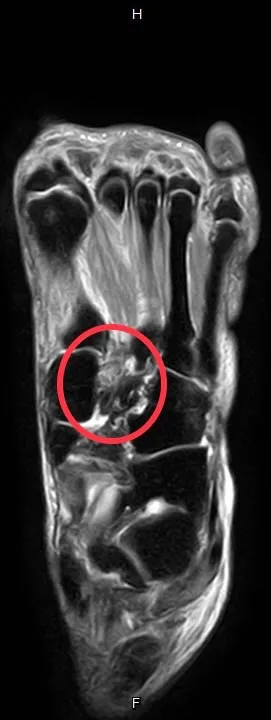

患者經MRI檢查發現蹠跗韌帶有受傷。大里仁愛醫院提供